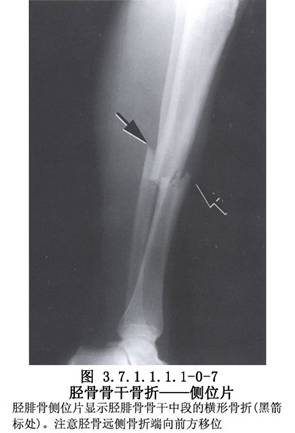

脛骨幹骨折不癒合有多種手術治療方法,需要根據骨折不癒合的類型、骨折對位對線及軟組織情況予以選擇。但要注意儘量選用方法較簡單,創傷小和局部血循環破壞少的手術。脛骨幹骨折影像表現及解剖見下圖(圖3.7.1.1.1.1-0-5~3.7.1.1.1.1-0-8)。